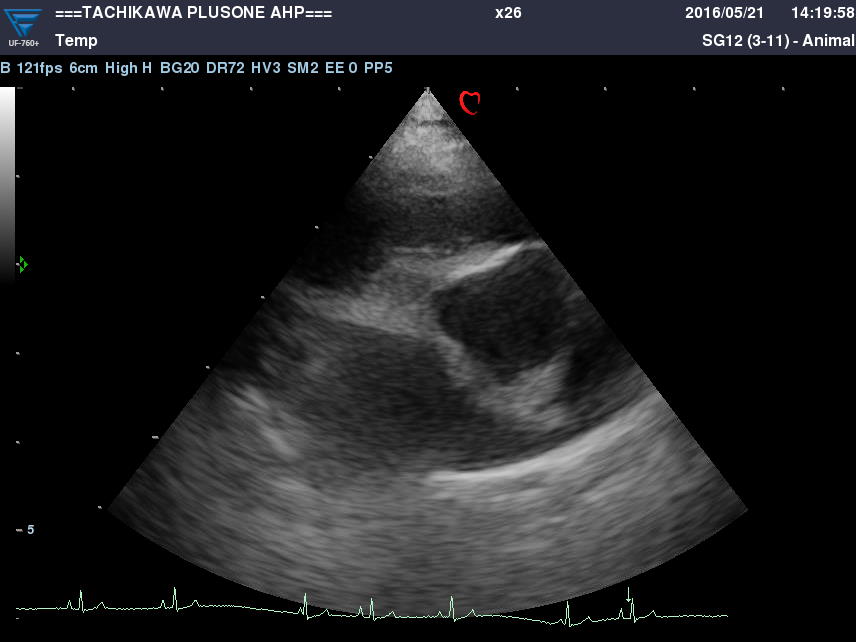

・心エコー検査(心超音波検査)

心臓の状態を把握し治療方針を決定するのに欠かせない検査です。

心臓の細部構造や動きの観察をします。

また、血液の流れる向きやスピードの計測が出来ます。